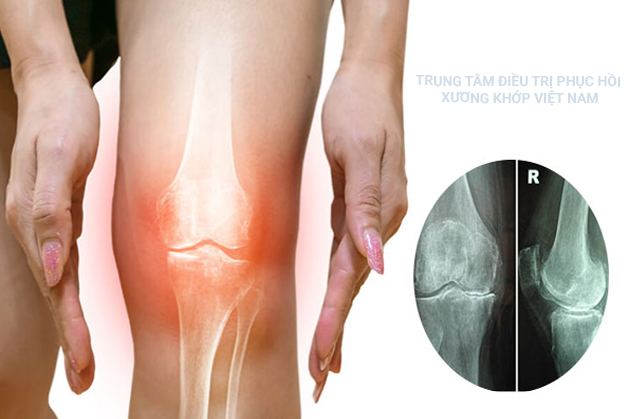

Hình 3: Hẹp khe khớp ở đầu gối (Ảnh minh họa)